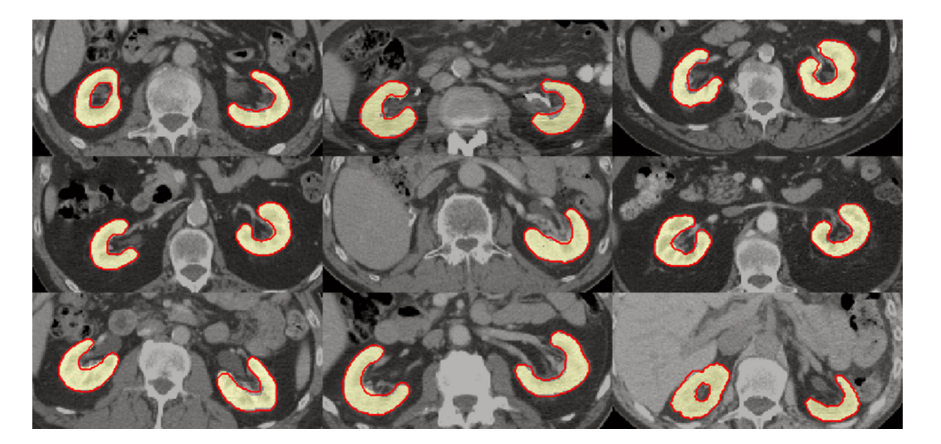

Figure 4. Examples of segmentations for nine patients in the test dataset. Yellow region represents manual segmentation, while red contour illustrates automated segmentation generated using method A5.

图 4 展示了测试数据集中九位患者的实例分割结果。其中,黄色区域表示人工标注的部分;而红色边界则对应于基于 A5 方法的自动生成